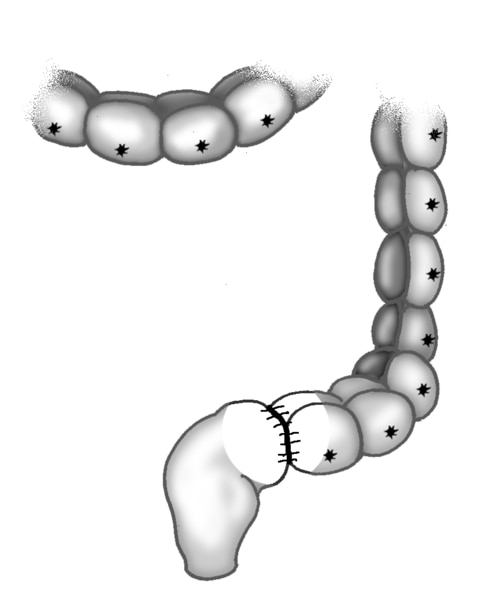

The Large Intestine, Rectum, and Anus after Pull-Through Surgery

Black and white illustration of the large intestine, rectum, and anus after pull-through surgery.

Illustration of the large intestine, rectum, and anus after pull-through surgery.

Black and white illustration of the large intestine, rectum, and anus after pull-through surgery.